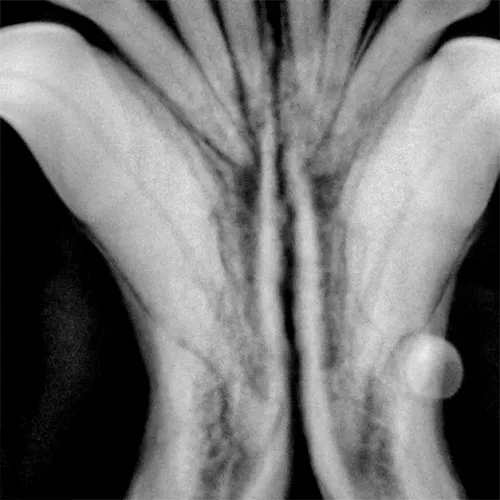

Intraoral radiograph of the rostral mandibles revealing advanced external resorption affecting both canine teeth